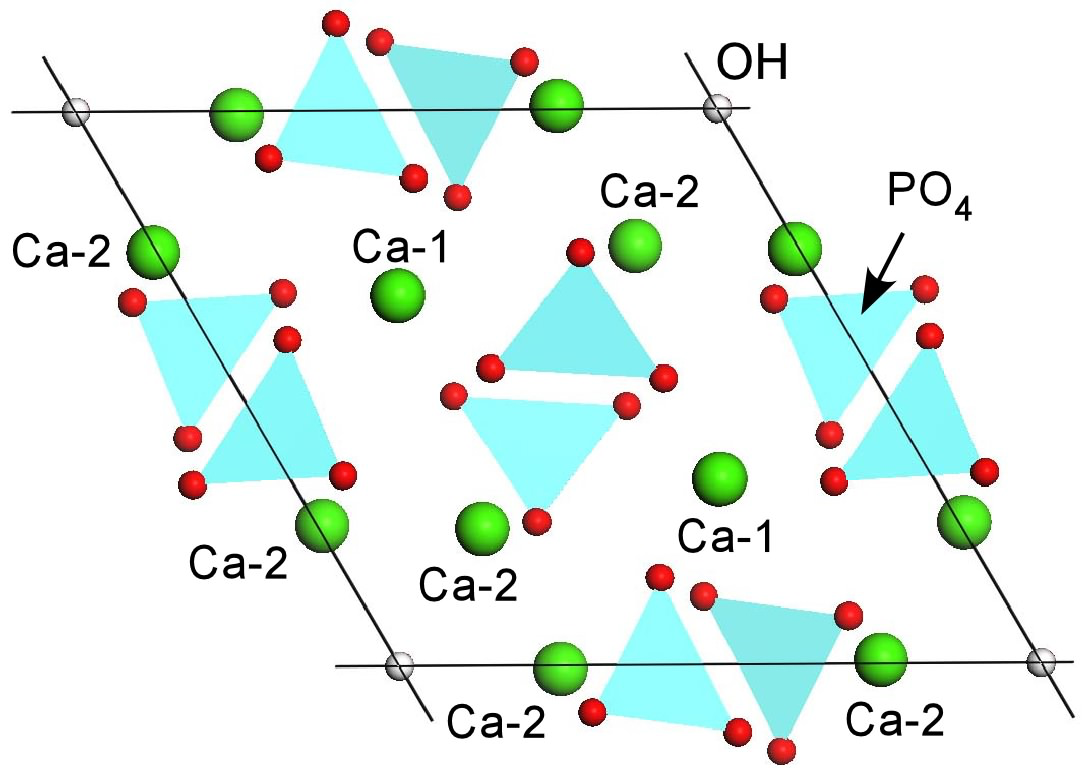

80代男性、左下7654、歯根面カリエスhttps://plaza.rakuten.co.jp/mabo400dc/diary/202106180001/前回の続きなのだが、フッ素の電気化学的な意味について語ろう。フッ素はハイドロキシアパタイト中のOH-:水酸基と置換してフルオロアパタイトとなり、水素イオン:プロトンの電導性を抑制すると思われる。なぜならハイドロキシアパタイト中の水素イオンの電導は水酸基が担っており、水酸基がなくなれば電導性が無くなるということだ。現代歯科医学でいわれているようにフルオロアパタイトは硬いので酸に溶けにくいという説明は間違っている。そもそも硬いのと酸に溶けにくいというのは別の話だ。後ろで弟子が定期試験の化学をしていたのをちょっと見たのだが、ちょうど電気分解の話だった。要するに虫歯というのは歯の電気分解ということなのだ。イオン化傾向の違う物質が酸性溶液中で回路を形成するとイオン化傾向の高い方が電子を奪われて溶ける。そういうことだ。歯のイオン化傾向は測定することができる。アルミと鉄と同じくらい、亜鉛より低いがその他のすべての金属よりも高い。しかし、フッ素がどの程度虫歯の抑制効果があるかというと僕の1年に渡る実験ではかなりしょぼい。というか、いくらフッ素塗布しても虫歯の進行を止めることはできなかった。ところが、重曹うがいでは1ヶ月で虫歯が治った。治ったと言ってもダイアグノデント値が改善したということなのだが。重曹うがいの方がフッ素塗布よりも桁違いに虫歯の予防効果は高いというのが実感だ。今回はたくさんある虫歯のうち一番ひどい左下7の頬側のカリエスを修復することにした。虫歯はどれも黒くなっているが、黒くなっている虫歯の進行は遅いので何もしなくても問題ないことが多い。この理由もフッ素と同じで、黒色物質:FeS:硫化鉄はイオン電導を遮断するので、虫歯になりにくいのだ。もう一つフッ素に関して言っておくことを忘れていたのだが、フッ素はハロゲン族と言って強い金属腐食作用がある。マイナスのイオン化傾向の高い物質で、金属から(カルシウム含む)電子を奪って溶かしてしまう。だから濃度の高いフッ素により歯が溶けることがあるのだ。これは歯牙フッ素症として知られている。フッ素の虫歯抑制効果と歯牙溶解効果との閾値がどのくらいかというのは、もしかしたらよく言われるように2ppmなのかもしれない。このような見解は従来の歯科医学では語られることがなかったのだが、それは電気化学的な視点が欠けているからだ。

80代男性、左下7654、歯根面カリエス虫歯とは何か?ということは知られていない。なぜ出来るのかは分からないので、対症療法に終始しているのが現状だ。この記事だけで全てを網羅することはできないと思うのだが、ちょっとだけ試みてみよう。虫歯というものは歯が酸に溶けたものというのが一般に言われているが、実は歯は酸には強い方だ。コーラ(pH3)に数週間浸けこんでも溶けてなくなったりはしない。なんとなく表面が柔らかくなったような気がするだけだ。歯学部では歯牙を酸で溶かす実験はしない。溶けないのは不都合な真実だからだ。現実問題として数週間もコーラを口の中に溜めておくことなどできはしない。ではなぜ溶けるかというとそれは電気化学的な腐食と考えると実に分かりやすい。電気化学的腐食というのは例えば鉄の赤錆のようなものだ。レモン電池の鉄の電極が錆びて銅の電極は錆びないとか、電車の線路の近くの水道管が錆びやすいと言った現象もそれだ。工業的には電解研磨と言って金属表面を一層とかしてピカピカにする技術は古くから知られている。金属の電気化学的腐食を検索してみると、虫歯は微生物腐食のカテゴリーに含まれるかもしれないが、その基本的な原因は少なくとも3つは挙げられる。1、酸素濃度差電池の形成による通気差腐食2、イオン化傾向の違いのある2つ以上の物質が酸性電解液にある場合の腐食電池の形成3、応力腐食割れのような絶え間ない応力の集中部位に微細なクラックが生じ腐食が進行するケースなどが考えられる。虫歯は歯根にできやすい。これはエナメル質より象牙質の方がイオン化傾向は高いので、象牙質が自動的にカソード:陰極:腐食電極になる。カソード:陰極というのは電子を奪われる部分が溶ける:腐食する:虫歯になるということだ。同じ一本の歯でも酸素濃度が低い部位がそうではない部位との間に相反する電極が生じる。酸素濃度が低いところがカソードになり溶ける。具体的には口の中でも奥の方:遠心がカソードになり溶けやすい。内側外側では酸素が足りない条件としては頬粘膜や舌によって酸素を遮断しやすい部分がカソードになり虫歯になりやすい。そのような部分の方が唾液もかかりにくく酸性になりやすいので腐食を進行させる。酸性つまり水素イオン:プロトンがなければそもそも虫歯になったりしない。歯:ハイドロキシアパタイトは水素イオン:プロトンだけを電導させるイオン電導セラミックスという物質なのだ。歯からプロトンが外に出るときにカルシウムと電子交換して電子を奪われたカルシウムが歯から溶出するのが虫歯の根本原因だからだ。唾液がよくかかるところも虫歯になりにくい。唾液には重炭酸塩(重曹成分)が含まれているので、水素イオンが中和されて水と二酸化炭素に変化する。だから虫歯になりにくいのだ。単に唾液で洗い流すということではない。これが頬側の画像だ内側:舌側舌側拡大つづく